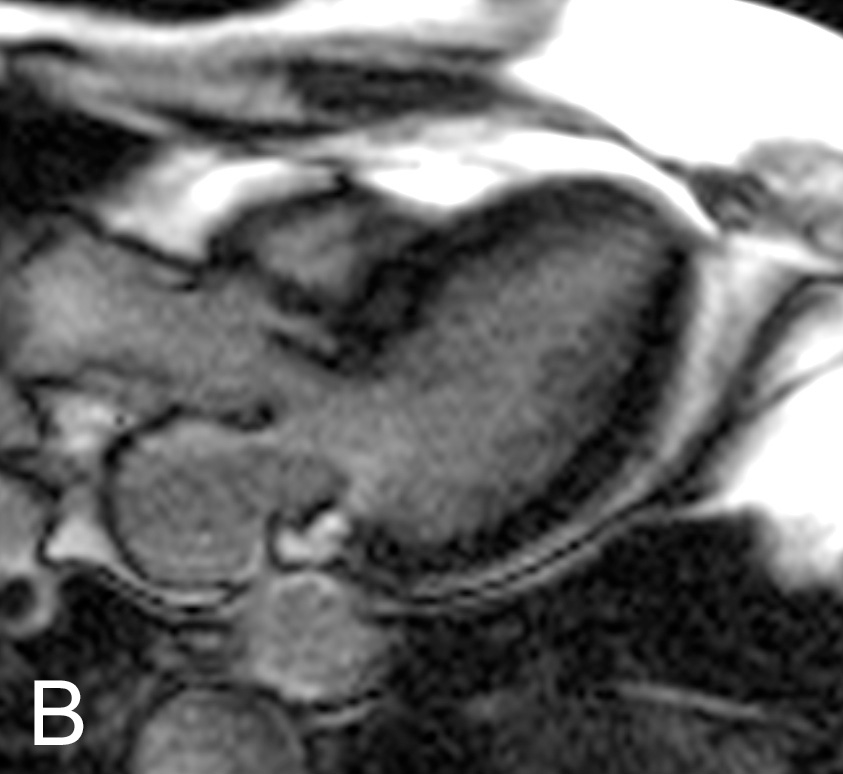

Figure 2

CMR and DE-CMR images.Fig. 2A: Short axis view of left ventricular myocardium without contrast showing an aspecific hypocaptation in the infero-basal portion. Fig. 2B: Long-axis DE-CMR images showing no late enhancement.

A 76-year-old woman was admitted for atypical chest pain and fatigue of 10 days’ duration. The clinical findings were irrelevant except for epigastric tenderness. The electrocardiogram (ECG) showed a borderline 0.1 mV horizontal ST depression in V4-V5 and minor ST abnormalities in V6, II, III and aVF leads (fig. 1). The chest radiography was normal. Blood analysis disclosed pathological levels of troponin-I (6.1ug/L; normal <0.30), total creatine phosphokinase (424 U/L; normal <167), creatine phosphokinase MB isoenzyme (84.1 µg/L, normal <3.4) and lactate dehydrogenase (243 U/L, normal <232). The leukocyte count was elevated (16.7 G/L, normal 4.0–10.0). Transthoracic echocardiography (TTE) showed a hyperkinetic left ventricle with a thickened interventricular septum and minimal pericardial effusion. Non-ST segment elevation myocardial infarction was diagnosed on the basis of the association of chest pain and a further increase of troponin-I (peak value 13.7 µg/L). The emergency angiogram showed normal coronary arteries. In the meantime, haematological study revealed persistent leucocytosis (peak value 19.9 G/L) with 67% eosinophilia, corresponding to an eosinophilic count of 13.2 G/L, elevation of eosinophil cationic protein (ECP; >200 µg/L, normal <16.0), IgE (685 kU/L, normal <100) as well as serum tryptase (12.2 µg/L, normal 1.0–11.4). Cardiac magnetic resonance (CMR) was performed on a Siemens Avanto 1.5T (Siemens Medical, Erlangen, Germany). The cine and delayed enhancement images (DE-CMR) revealed only aspecific hypocaptation in the infero-basal portion of left ventricular myocardium, without late enhancement (fig. 2). As further workup we performed a myocardial biopsy demonstrating an important sub-endocardial eosinophilic infiltrate with fibrin deposition and focal extension into the myocardium (fig. 3 A, B). Numerous intra- and perivascular eosinophils were also present in the interstitium. An extended aetiological workup was performed. The patient had a history of recurrent sinusitis and allergy to pollen and asthma. A solid neoplastic process was ruled out by thoraco-abdominal CT scan. Screening for parasites in the serum and stools was negative, as were serological tests for antibodies to viruses and biopsy for a myocardial infection. Haematological screening showed normal beta2-microglobulin and vitamin B12, no FIP1L1-PDGFRA mutation and normal immunoelectrophoresis. The immunological workup for vasculitis (ANCA, antimyeloperoxydase and anti-proteinase 3) was negative. On the basis of asthma, recurrent sinusitis, hypereosinophilia and the results of the heart biopsy, Churg-Strauss syndrome was diagnosed (table 1). Pulse endovenous corticosteroid treatment (500 mg i.v. prednisolone) was started just after the cardiac biopsy. At day 1 levels of blood eosinophils dropped to 0.4 G/L and the ECP level returned to normal values. The hospital course was uneventful and 3 months later the patient was still asymptomatic with a normal eosinophil count on oral prednisone.

The cardiovascular imaging workup in the presence of hypereosinophilia and suspected heart involvement includes the ECG, which may show non-specific conductance disturbances or, very rarely, patterns typical of acute coronary syndromes due to coronary vasospasm [10, 11] or intracoronary thrombi [12]; TTE, which may be normal or show contractility impairment, ventricular wall thickness, and presence of intracardiac thrombi or pericardial effusion; CMR and DE-CMR, which may confirm and characterise myocardial necrosis [13], inflammation [14] or fibrosis [15, 16]. Nevertheless, if the myocardial involvement occurs in the early phase, as in this case, the CMR may be non-contributive and only endomyocardial biopsy is diagnostic and usually mandates the indication for immunosuppressive treatment.